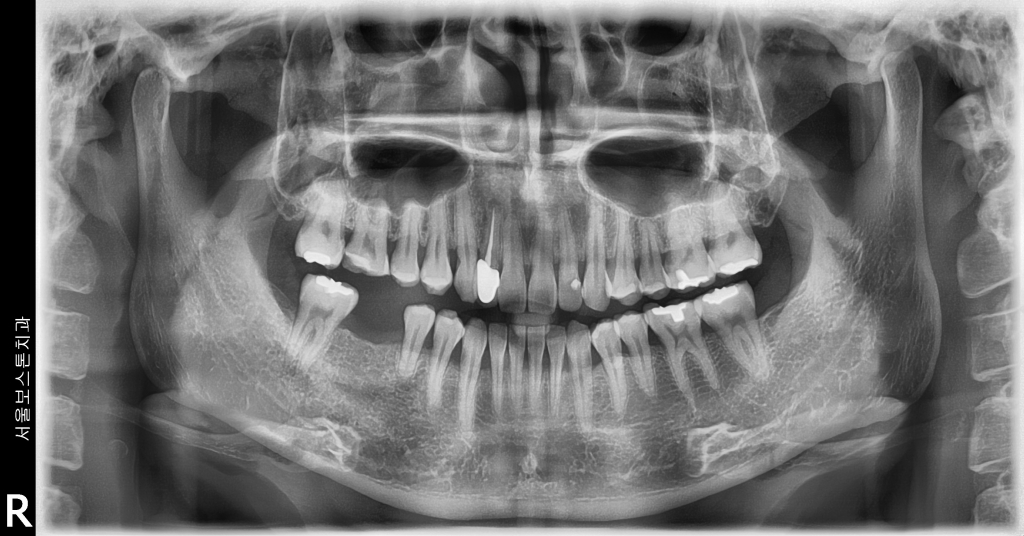

서울보스톤치과에서 치료 받으신 분들의 전후사진입니다.